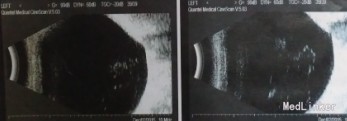

查体: VOD 0.9,VOS:0.8,双眼中央前房4CT,周边1/2CT,虹膜纹理清,瞳孔3×3mm,晶体混浊++。眼底 C/D约0.8。双眼房角开。 辅查: 右眼视盘视神经纤维层下方厚度变薄

诊断:双眼开角型青光眼 治疗:右眼小梁切除术